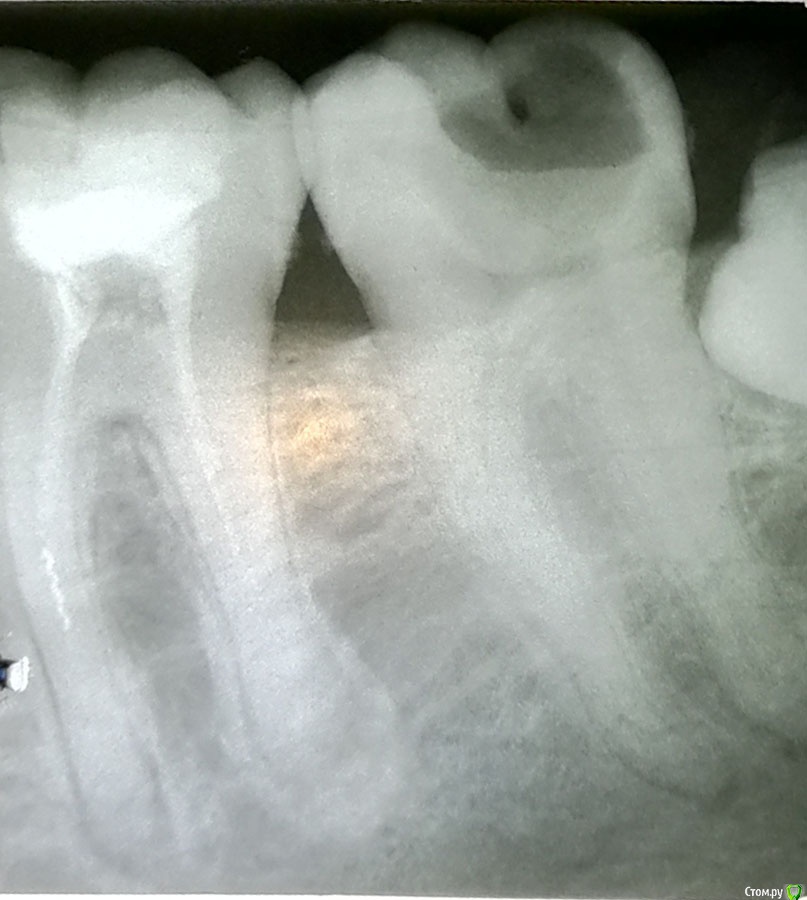

qwerty54321 Опубликовано 5 октября, 2019 Поделиться Опубликовано 5 октября, 2019 Добрый день!Подскажите, пожалуйста, можно ли сохранить зуб или только удаление (на снимке справа)? Ссылка на комментарий

DmitrySH Опубликовано 5 октября, 2019 Поделиться Опубликовано 5 октября, 2019 Здравствуйте. в зубе 36 требуется ревизия каналов под контролем микроскопа.37 - можно и нужно лечить38 - удалять обязательно Ссылка на комментарий